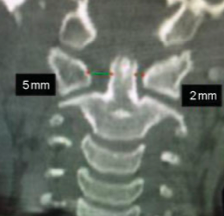

Qual é o exame radiográfico chave para a Síndrome de Grisel?

RX Transoral, que avalia a presença de assimetria no espaço entre o odontóide e as massas laterais de C1.

Como a Tomografia Computadorizada é usada na Síndrome de Grisel?

Fornece informações detalhadas sobre a posição das vértebras C1 e C2.

Quais são os sinais radiográficos importantes na Síndrome de Grisel?

Assimetria no espaço entre o odontóide e as massas laterais de C1 e o Wink Sign.